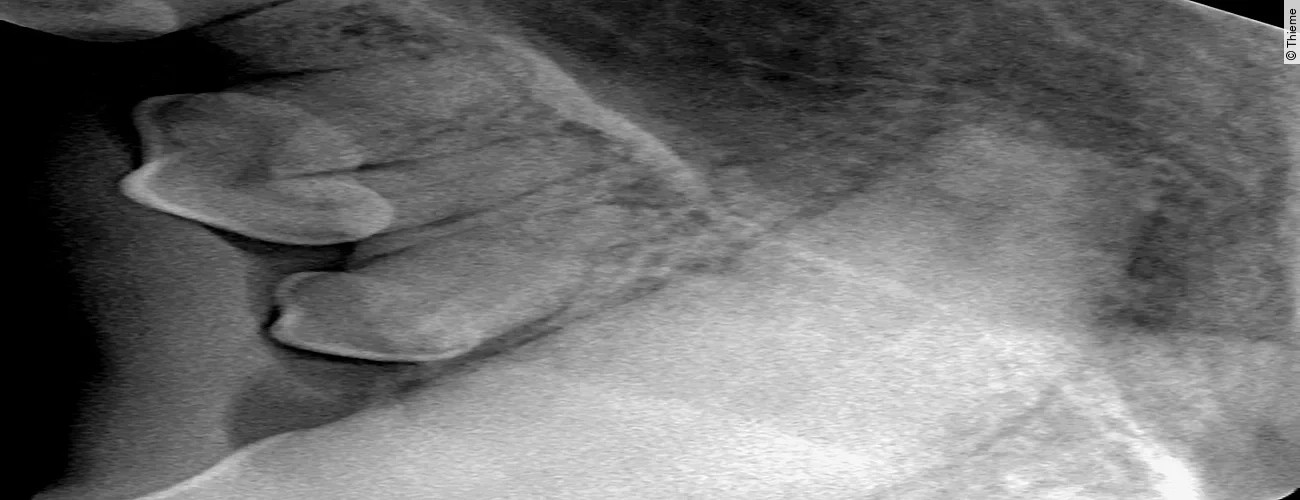

Replantation nach Avulsion Oberkieferfangzahn rechts

Der Originalartikel „Avulsion Oberkieferfangzahn rechts“ stammt aus dem Bild-Atlas der Zahnbehandlungen Hund und Katze; 2. aktualisierte Auflage; 2022.